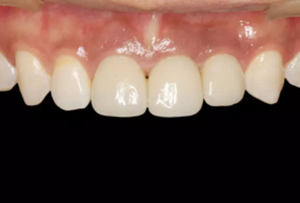

圖23 最終修復(fù)后即刻口內(nèi)像

圖25 最終修復(fù)后復(fù)查口內(nèi)像

(5)復(fù)查。種植體周圍骨水平穩(wěn)定,齦乳頭及齦高點位置穩(wěn)定,齦緣 曲線形態(tài)理想,唇側(cè)軟硬輪廓良好,功能滿意,修復(fù)效果符合預(yù)期。